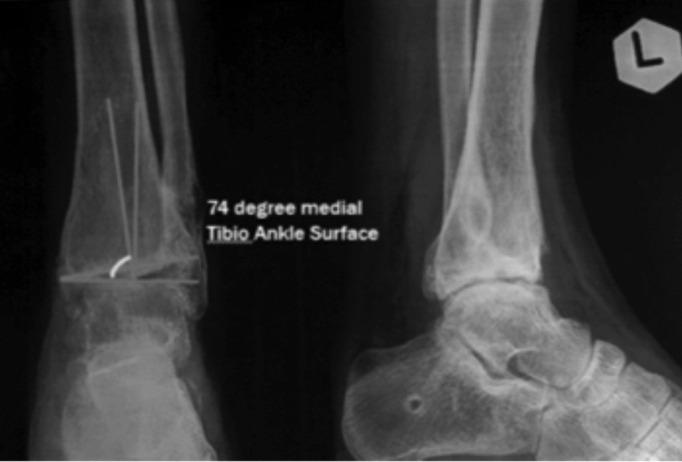

In Indonesia, arthrodesis becomes a choice of treatment in the absence of ankle arthroplasty implants for young adults. Arthrodesis on ankle osteoarthritis (OA) often leads to functional impairment. Low tibiofibular osteotomy is an alternative and it has been known to be the preferable option for those in the productive-ages. A 22-year-old male with a previous history of a motorbike accident, operated eight years ago, came with persistent pain on the left ankle that has worsened over the years. Plain radiography with a tibial-ankle surface angle (TAS) of 74 (normally 88-93) indicated varus deformity. Osteotomy was performed on distal tibia above the syndesmotic joint, as well as on the middle third of fibula. Open wedge osteotomy of the tibia was corrected until the normal TAS angle was reached by fluoroscopy. Cortical allograft was used to fill the osteotomy gap. Instrumentation was performed using a clover leaf® plate with 6 screws insertion for fixation stability. All results were satisfactory. Twelve weeks post-operatively, the patient was performing activities normally. Four-month post-operative radiological evaluation showed fusion of graft and the angle of TAS of 89°. Post-operative functional assessment using the American Academy of Orthopaedic Surgeon (AAOS) Foot and Ankle Measurement (FAM) questionnaires showed significant improvement (pre 89, post 38).

在印度尼西亚,对于没有踝关节置换植入物的年轻成年人来说,关节融合术成为一种治疗选择。踝关节骨关节炎(OA)的关节融合术常常导致功能障碍。下胫腓截骨术是一种替代方法,并且已知对于处于生产年龄的人来说是更可取的选择。一名22岁男性,有8年前摩托车事故史,前来就诊,其左脚踝持续疼痛,多年来逐渐加重。胫骨-踝关节表面角(TAS)为74(正常为88 - 93)的X线平片显示内翻畸形。在距下联合上方的胫骨远端以及腓骨中三分之一处进行截骨术。通过透视将胫骨的开放楔形截骨矫正至正常TAS角。使用皮质骨同种异体骨填充截骨间隙。使用三叶形®钢板并插入6枚螺钉进行内固定以确保稳定性。所有结果均令人满意。术后12周,患者活动正常。术后4个月的影像学评估显示移植骨融合,TAS角为89°。使用美国矫形外科医师学会(AAOS)足踝测量(FAM)问卷进行的术后功能评估显示有显著改善(术前89分,术后38分)。